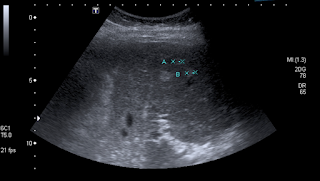

Paciente de 72 años con antecedente de tuberculosis genitourinaria hace 40 años.